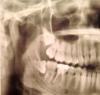

Yuls Опубликовано 18 января, 2013 Поделиться Опубликовано 18 января, 2013 Добрый день, 4 мес назад удалила сложный зуб мудрости внизу, зажило все хорошо, никаких проблем не было, ничего не беспокоит и по сей день. Сделала снимок по другому вопросу и обнаружила, что на месте удаления что-то осталось - это осколок зуба? Если да, то что теперь с этим делать и чем это опасно? Планирую беременность, поэтому хотелось бы узнать и влияние этого на беременность. Заранее большое спасибо. Ссылка на комментарий

kriokov Опубликовано 18 января, 2013 Поделиться Опубликовано 18 января, 2013 нет осколка, нормально все Ссылка на комментарий

kama2005 Опубликовано 18 января, 2013 Поделиться Опубликовано 18 января, 2013 6ку перелечить лучше, верхнюю восьмерку тож на удаление... 1 Ссылка на комментарий

Yuls Опубликовано 18 января, 2013 Автор Поделиться Опубликовано 18 января, 2013 (изменено) Спасибо за оперативный ответ)) А что это за "крюк" на месте зуба на втором и третьем снимке может быть? Изменено 18 января, 2013 пользователем Yuls Ссылка на комментарий

Yuls Опубликовано 18 января, 2013 Автор Поделиться Опубликовано 18 января, 2013 6ку перелечить лучше, верхнюю восьмерку тож на удаление... Да, насчет 6ки знаю, что там киста, - это просто перепломбировать канал или лечить кисту как-то? Не хочется зуб терять((. А верхних 8ок у меня две таких, но удалять пока побаиваюсь или уже критично? Спасибо. Ссылка на комментарий

kriokov Опубликовано 18 января, 2013 Поделиться Опубликовано 18 января, 2013 Спасибо за оперативный ответ)) А что это за "крюк" на месте зуба на втором и третьем снимке может быть?зто кость челюсти , просто так выглядит на снимке. имхо Ссылка на комментарий

Yuls Опубликовано 18 января, 2013 Автор Поделиться Опубликовано 18 января, 2013 (изменено) Еще вопросик: а затемнение на месте этого злосчастного 8го зуба - это что? Изменено 18 января, 2013 пользователем Yuls Ссылка на комментарий

kriokov Опубликовано 18 января, 2013 Поделиться Опубликовано 18 января, 2013 Еще вопросик: а затемнение на месте этого злосчастного 8го зуба - это что?место в кости, где зуб ранее находился, именно так на снимке после удаления и выглядит Ссылка на комментарий

АнтонТЛТ Опубликовано 18 января, 2013 Поделиться Опубликовано 18 января, 2013 Спасибо за оперативный ответ)) А что это за "крюк" на месте зуба на втором и третьем снимке может быть?Вероятно это межкорневая перегородка Ссылка на комментарий

Yuls Опубликовано 20 января, 2013 Автор Поделиться Опубликовано 20 января, 2013 Вероятно это межкорневая перегородка а что это за перегородка - она должна была остаться? я волнуюсь, чтоб это не дало о себе знать потом, чтоб все было чисто Ссылка на комментарий

Bier Опубликовано 21 января, 2013 Поделиться Опубликовано 21 января, 2013 а что это за перегородка - она должна была остаться? я волнуюсь, чтоб это не дало о себе знать потом, чтоб все было чистоДа, это часть челюсти Ссылка на комментарий